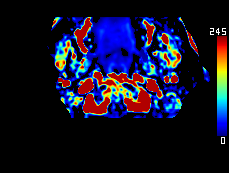

DeepClue-Precise CT 측부혈류영상

Perfusion CT를 이용한 측부혈류영상

동맥기

모세혈관기

조기정맥기

후기정맥기

지연기